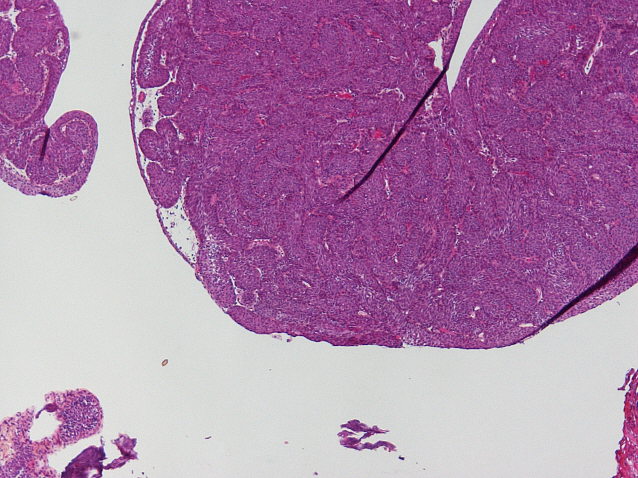

Bladder Papillary Lesions

Case ID: 464